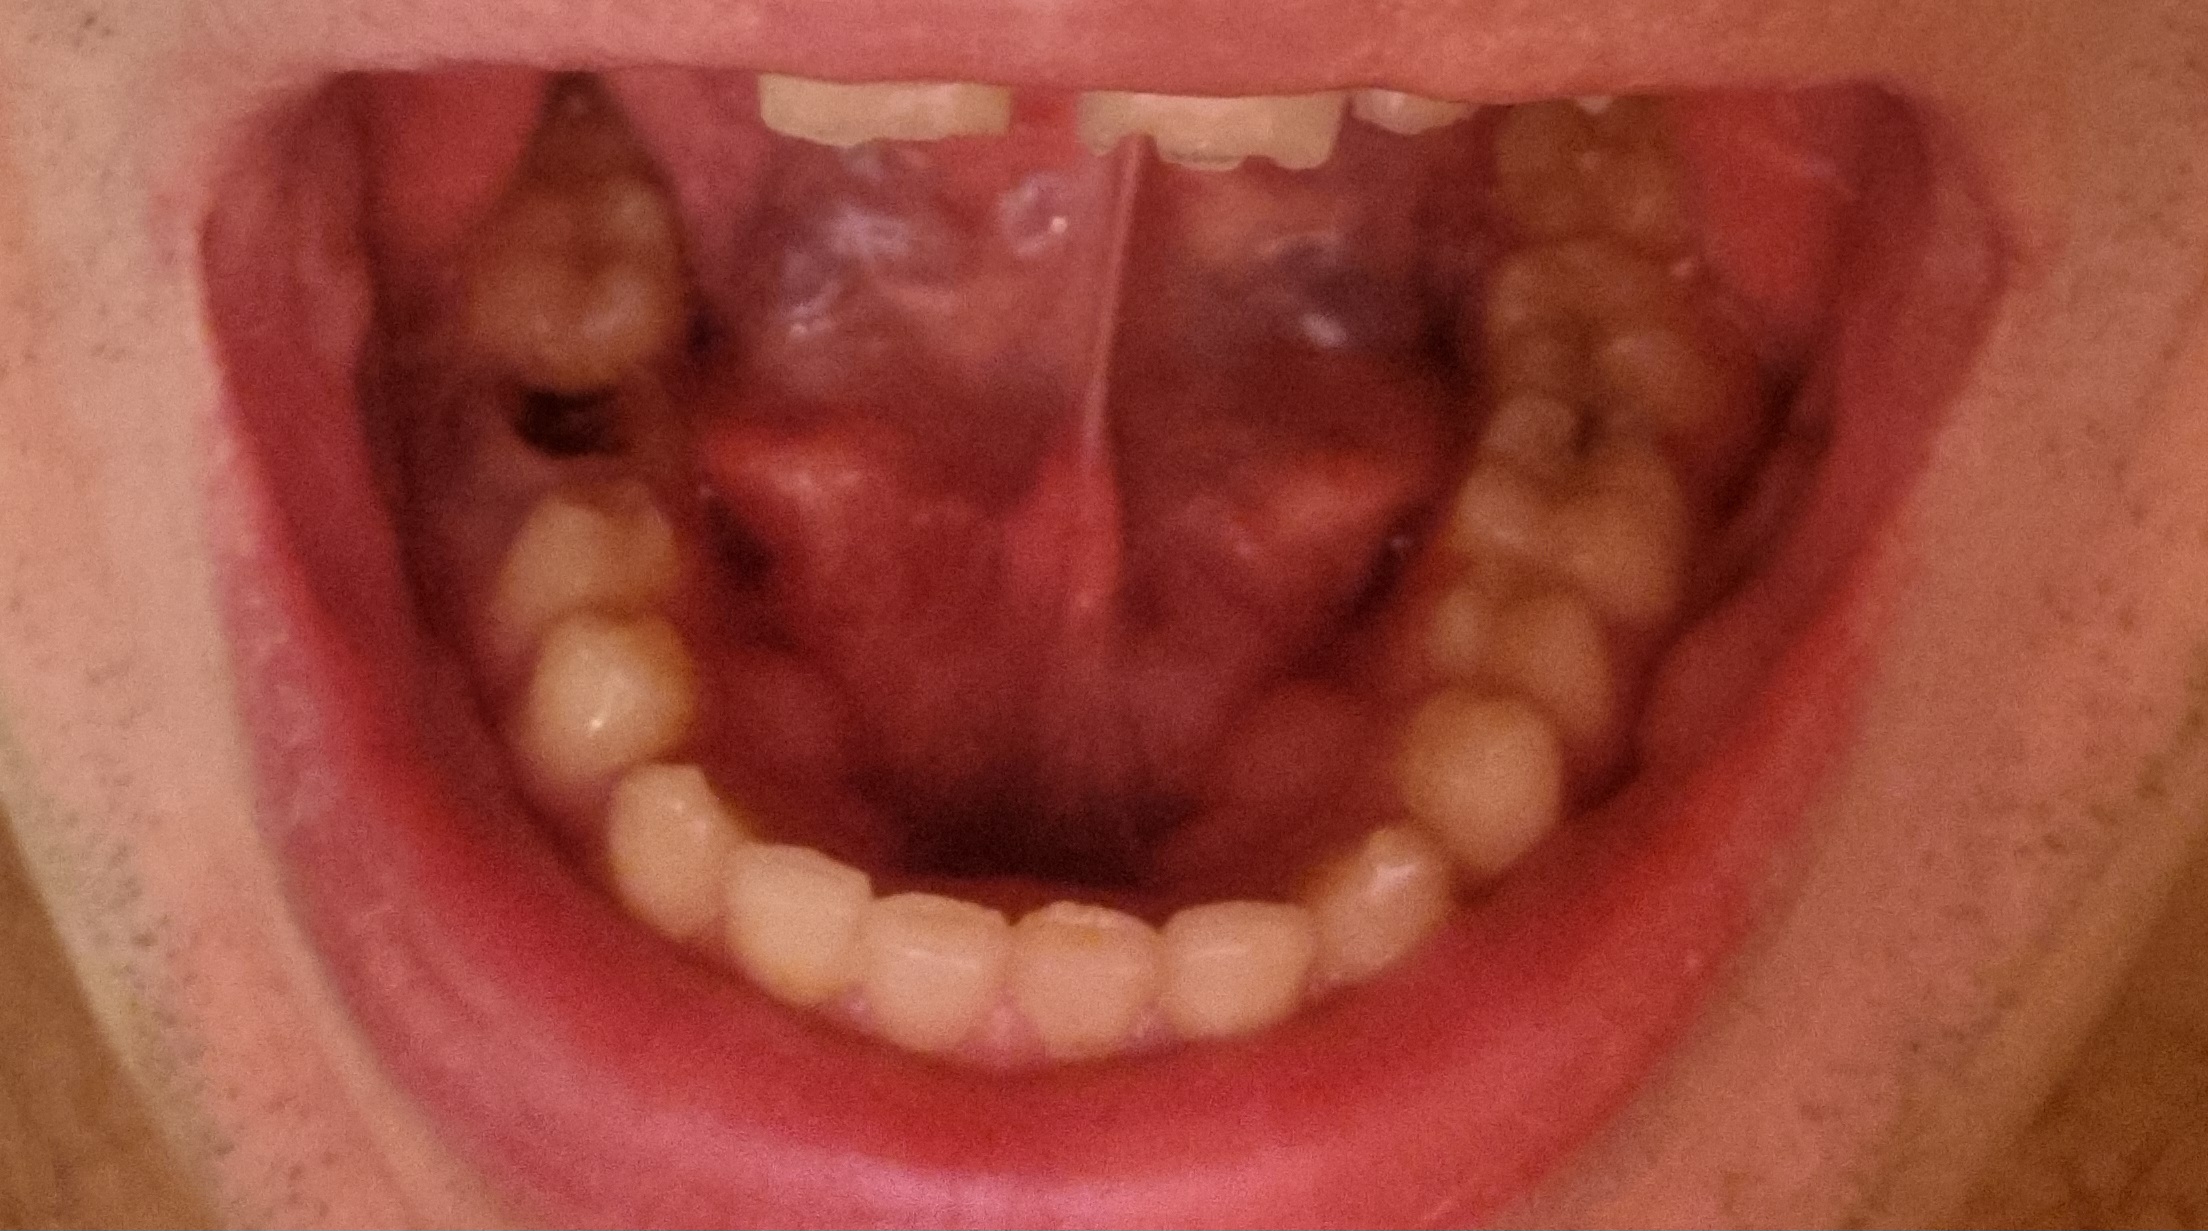

1000070960.jpg 313Кб, 1117x832

1117x832

1000070961.jpg 180Кб, 882x704

882x704

Зуб пятерка. Возможно такое вылечить, анонче? Отклолся как то, вообще не болит.